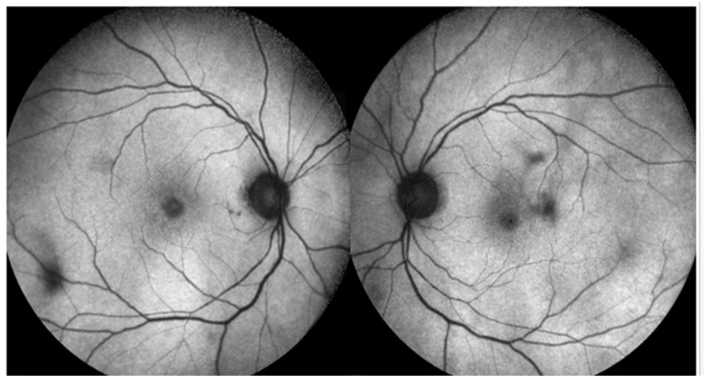

A 70 year old lady, incidentally detected to have an endometrial carcinoma Stage 3 on an executive check up, came to us with defective vision and photopsiae of both eyes of ten days duration. She was asymptomatic otherwise and thus had not taken any treatment for her gynaecological condition. Initial visual acuity was 20/80 (distance),20/200 (near) in both eyes. Pupils were sluggish binocularly; however there was no relative afferent pupillary defect. Colour vision was impaired (0/21 both eyes). Fundus was unremarkable except retinal pigment epithelium mottling at the macula.(Figure-1). Visual fields were severely depressed in both eyes (Fig. 2, Fig. 3). Magnetic Resonance Imaging (MRI)of the Brain & Orbits were normal; with no evidence of metastasis. All investigations including laboratory tests for posterior uveitis and vasculitis were done and were negative. Visual acuity worsened to Counting fingers close to face both eyes the next day. Fundus Auto Fluorescence (FAF) showed patchy hyperautofluorescence in both eyes (Figure-4). OCT Macula showed diffuse loss of ellipsoid zone (EZ), external limiting membrane (ELM), outer nuclear and plexiform layers in both eyes, except subfoveally; where EZ and ELM were faintly visible (Fig. 6, Fig. 7). Visually Evoked Potentials (VEP) both eyes showed poor waves with normal P2 latency. Electroretinography (ERG) both eyes revealed flat scotopic and photopic responses (Fig. 8, Fig. 9). Intravenous methylprednisolone 1g for 5 days was administered followed by oral steroids. Vision improved to 20/25 (distance),20/40 (near) in right eye and 20/40 (distance), 20/40 (near)in left eye respectively. Diagnosis of Cancer Associated Retinopathy (CAR) was confirmed by detection of Antirecoverin antibody (Athena Diagnostics, MA 01752,USA). Patient underwent Endometrial carcinoma surgery (Staging laparotomy with Total hysterectomy + Bilateral Salpingo-oopherectomy + removal of tumour with pelvic and para-aortic lymphnodes), radiotherapy and chemotherapy and is currently on maintenance dose of oral steroids. FAF on follow up (after 6 weeks of systemic steroid therapy) showed diffuse area of hypoautoflourescene; indicating the area of damaged retinal pigment epithelium about 1disc diameter beyond the arcades in both eyes (Figure-5). Follow up OCT of macula showed clear reappearance of ellipsoid zone (EZ) and external limiting membrane (ELM) subfoveally, where it was faintly visible previously; explaining the improvement in vision.(Fig. 6, Fig. 7); however there was no evidence of ellipsoid zone (EZ)and external limiting membrane (ELM) in the areas deficient pre-treatment. Correlating the macular hypoautoflurescence on FAF at follow up with macular OCT, we found persistent diffuse loss of outer retinal layers (ellipsoid, ELM, ONL, OPL) in both eyes. The ONL and OPL loss was more significant temporally than nasally, probably emphasising the need for careful examination of temporal retina to detect early outer retinal involvement. ERG responses continued to be grossly reduced in both eyes even after visual recovery.

Fig. 1.

Multicolour Fundus Picture Both eyes.

Fig. 4.

Fundus Auto Fluorescence before treatment showing patchy hyperautofluorescence.

Fig. 5.

Fundus Auto Fluorescence post treatment showing diffuse area of hypoautoflurescene (beyond the blue marking) corresponding to the areas of damaged RPE. (For interpretation of the references to colour in this figure legend, the reader is referred to the Web version of this article.)